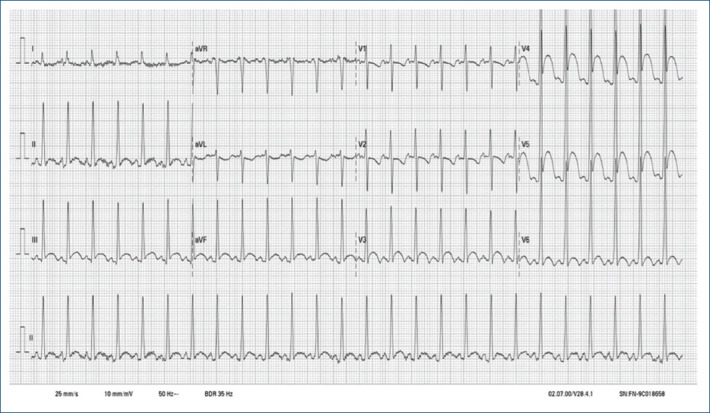

[Giant cardiac rhabdomyoma: an atypical cause of ST-segment elevation in the newborn].

{"title":"[Giant cardiac rhabdomyoma: an atypical cause of ST-segment elevation in the newborn].","authors":"Martín Negreira-Caamaño, Laura Acero-García de la Santa, Daniel Salvo-Chabuel, María Arántzazu-González-Marín","doi":"10.24875/ACM.23000195","DOIUrl":null,"url":null,"abstract":"","PeriodicalId":93885,"journal":{"name":"Archivos de cardiologia de Mexico","volume":" ","pages":"533-534"},"PeriodicalIF":0.0000,"publicationDate":"2024-07-18","publicationTypes":"Journal Article","fieldsOfStudy":null,"isOpenAccess":false,"openAccessPdf":"https://www.ncbi.nlm.nih.gov/pmc/articles/PMC12148531/pdf/","citationCount":"0","resultStr":null,"platform":"Semanticscholar","paperid":null,"PeriodicalName":"Archivos de cardiologia de Mexico","FirstCategoryId":"1085","ListUrlMain":"https://doi.org/10.24875/ACM.23000195","RegionNum":0,"RegionCategory":null,"ArticlePicture":[],"TitleCN":null,"AbstractTextCN":null,"PMCID":null,"EPubDate":"","PubModel":"","JCR":"","JCRName":"","Score":null,"Total":0}